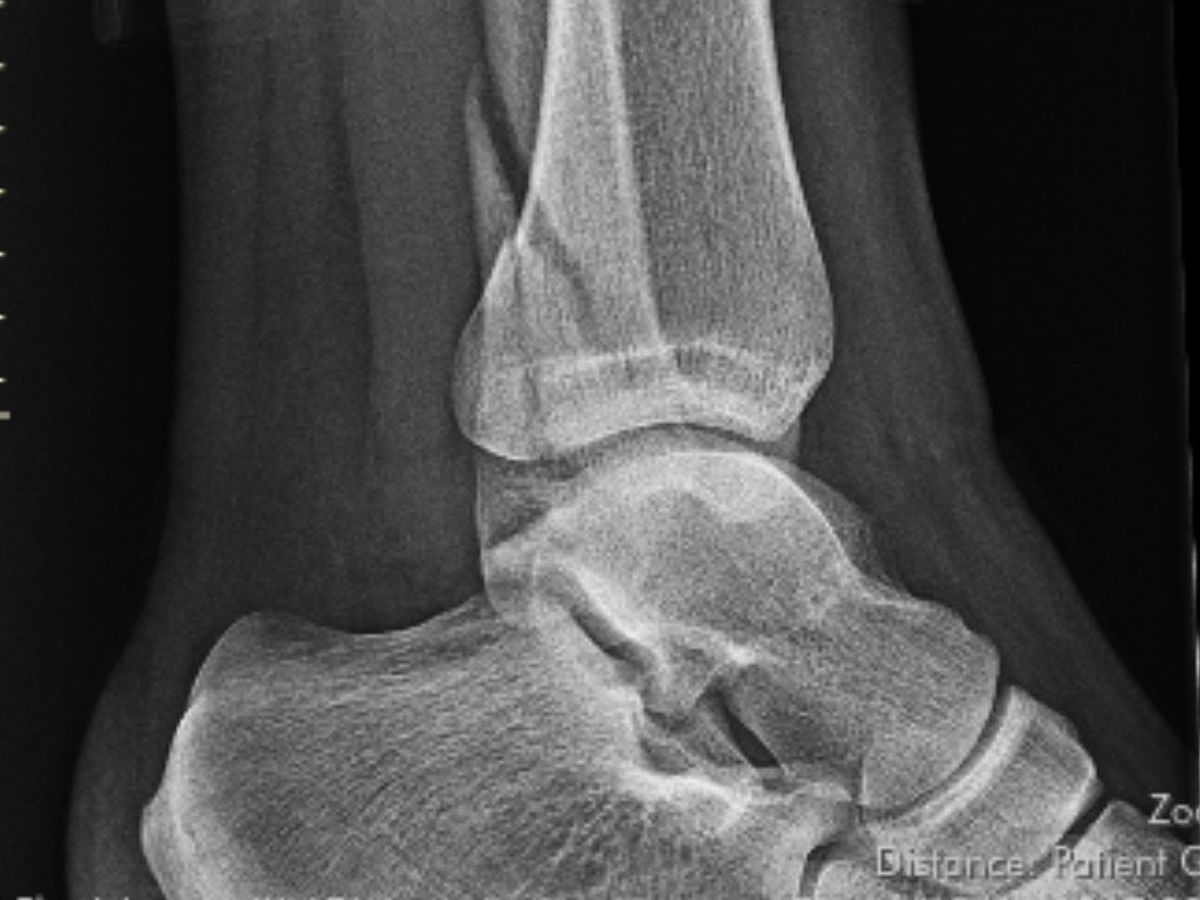

On 12/14/24 my Daughter fell and broke her ankle at 22 weeks pregnant. She was recommended surgery but with being pregnant & the difference in recovery times she opted out and has been home healing in a hard cast. She lives alone with her 3 dogs, and also her growing baby (27 weeks now) & pays all her bills off of a server/bartender income. Since the injury she has been off work. After applying for help she has been denied Short Term Disability, Unemployment, and also lost her insurance at the 1st of the new year. She is really stressed with all of her nonstop bills: rent, utilities, phone, food & dog food, etc with having no income or way to get income currently.